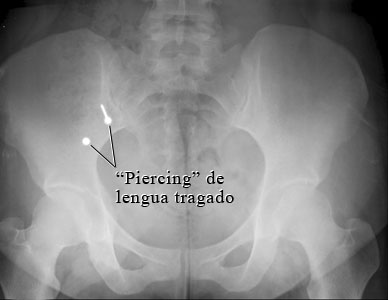

Imagen de un "piercing" de lengua tragado

Cortesía de Intermountain Medical Imaging, Boise, Idaho.

Esta radiografía del estómago muestra dos partes de metal dentro del intestino que fueron tragadas como consecuencia de una perforación en la lengua. El pendiente filoso podría causar problemas, mientras que es probable que la parte sin filo no cause problemas. Es probable que ambas partes se eliminen en las heces.